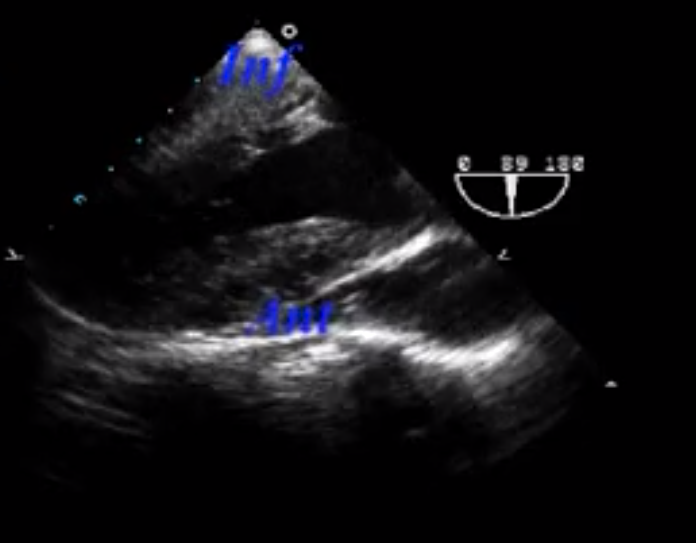

What walls of the heart are shown here?

INFERIOR = CLOSE TO THE PROBE

ANTERIOR = AWAY FROM THE PROBE

What papillary muscle is seen here?

Posteromedial Papillary Muscle